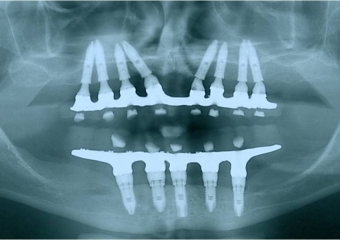

Rx dos implantes Cone Morse superiores

Raio X final